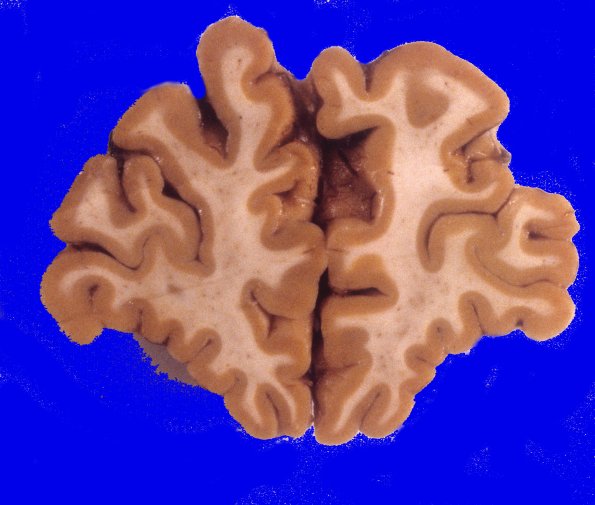

Neuronal Ceroid Lipofuscinosis (NCL)

3A2 Neuronal Ceroid Lipofuscinosis (Case 3) A7